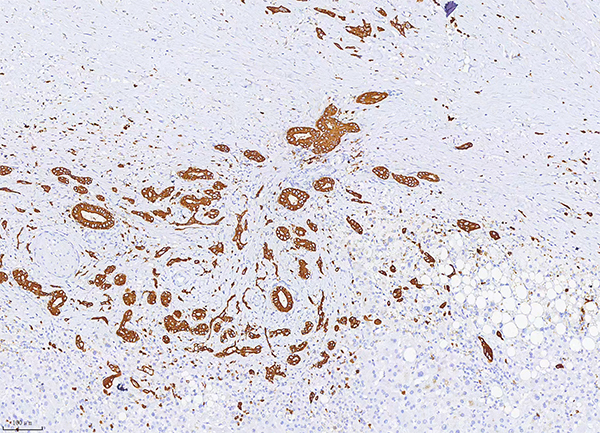

4.CK19分子量為40kDa,主要存在上皮和各種上皮來源的腫瘤中,特別是單層上皮和間皮,是驗證上皮分化的一個很好的標(biāo)志物。肝細(xì)胞不表達(dá)CK19,而膽管上皮表達(dá),因此CK19可用于肝細(xì)胞癌與肝內(nèi)膽管癌、轉(zhuǎn)移型腺癌的鑒別診斷。

陽性部位:細(xì)胞質(zhì)

樣本類型:肝內(nèi)膽管細(xì)胞癌